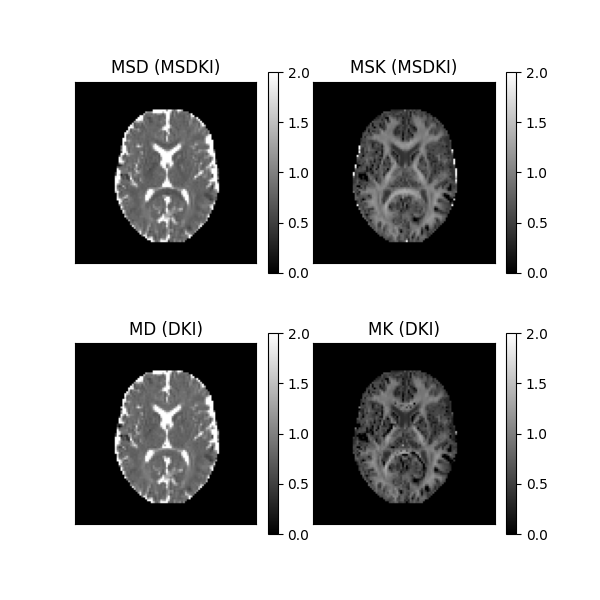

Let’s now visualize the data using matplotlib for a selected axial slice.

axial_slice = 9

fig2, ax = plt.subplots(2, 2, figsize=(6, 6), subplot_kw={"xticks": [], "yticks": []})

fig2.subplots_adjust(hspace=0.3, wspace=0.05)

im0 = ax.flat[0].imshow(

MSD[:, :, axial_slice].T * 1000, cmap="gray", vmin=0, vmax=2, origin="lower"

)

ax.flat[0].set_title("MSD (MSDKI)")

im1 = ax.flat[1].imshow(

MSK[:, :, axial_slice].T, cmap="gray", vmin=0, vmax=2, origin="lower"

ax.flat[1].set_title("MSK (MSDKI)")

im2 = ax.flat[2].imshow(

MD[:, :, axial_slice].T * 1000, cmap="gray", vmin=0, vmax=2, origin="lower"

ax.flat[2].set_title("MD (DKI)")

im3 = ax.flat[3].imshow(

MK[:, :, axial_slice].T, cmap="gray", vmin=0, vmax=2, origin="lower"

ax.flat[3].set_title("MK (DKI)")

fig2.colorbar(im0, ax=ax.flat[0])

fig2.colorbar(im1, ax=ax.flat[1])

fig2.colorbar(im2, ax=ax.flat[2])

fig2.colorbar(im3, ax=ax.flat[3])

plt.show()

fig2.savefig("MSDKI_invivo.png")

MSDKI measures (upper panels) and DKI standard measures (lower panels).

This figure shows that the contrast of in-vivo MSD and MSK maps (upper panels) are similar to the contrast of MD and MSK maps (lower panels); however, in the upper part we ensure that direct contributions of fiber dispersion were removed. The upper panels also reveal that MSDKI measures are let sensitive to noise artefacts than standard DKI measures (as pointed by [5]), particularly one can observe that MSK maps always present positive values in brain white matter regions, while implausible negative kurtosis values are present in the MK maps in the same regions.